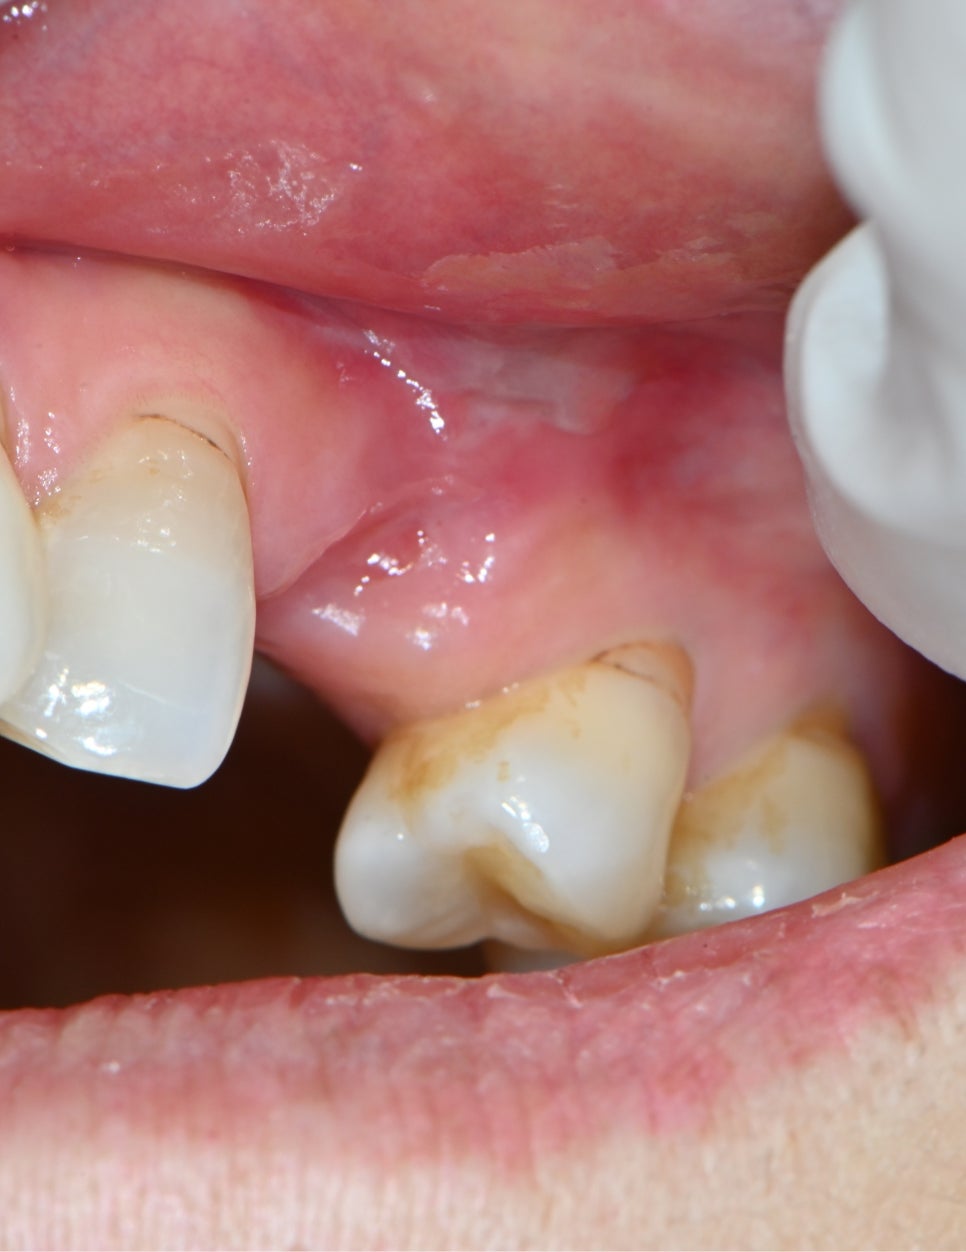

📸 Progress photo

Photo after removal of osteomyelitis

First, we partially removed the inflammation and provided medication treatment while observing the progress.

The gum swelling and pus gradually decreased,